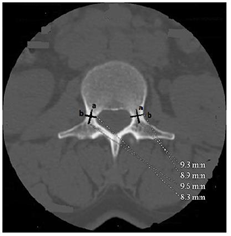

Figure 1. Axial section of the L3 lumbar vertebra passing through the pedicles (body and spinal canal dimensions). e: anteroposterior diameter of the vertebral body (DAPCV); f: transverse diameter of the vertebral body (DTCV); g: interpedicular distance of the spinal canal (DIP); h: anteroposterior diameter of the spinal canal (DAPCR).

2) Dimensions of the spinal canal

The anteroposterior diameter varied very little from L1 to L5, and there was no significant difference in sex (p = 0.3) (Figure 1). The interpedicular distance gradually increased from L1 to L5 with significantly higher values in men than in women (p < 0.001). These values are shown in Table 2 below.